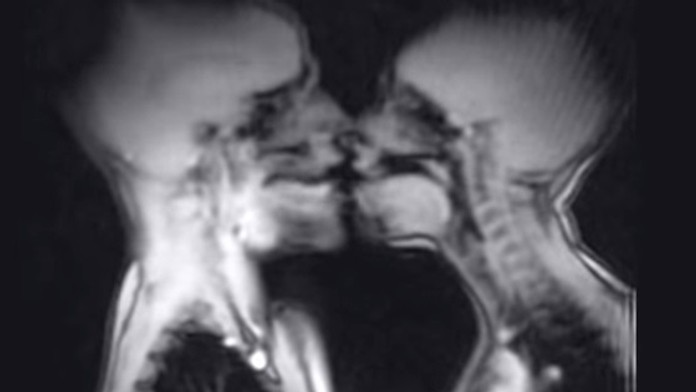

Internetom koluje šokujúce video. Zaujímalo vás niekedy, čo sa deje počas pohlavného styku v tele človeka? Sledujte! Zábery pochádzajú z magnetickej rezonancie a zachytávajú francúzsky bozk a splynutie muža a ženy takisto.

Video zverejnil portál HuffingtonPost.com a v jeho závere vidieť aj dieťa v tele matky, dokonca samotný pôrod. Za akých okolností zábery vznikli, nie je jasné. Vôbec však nie je vylúčené, že tvorcovia si pomohli počítačovou animáciou.